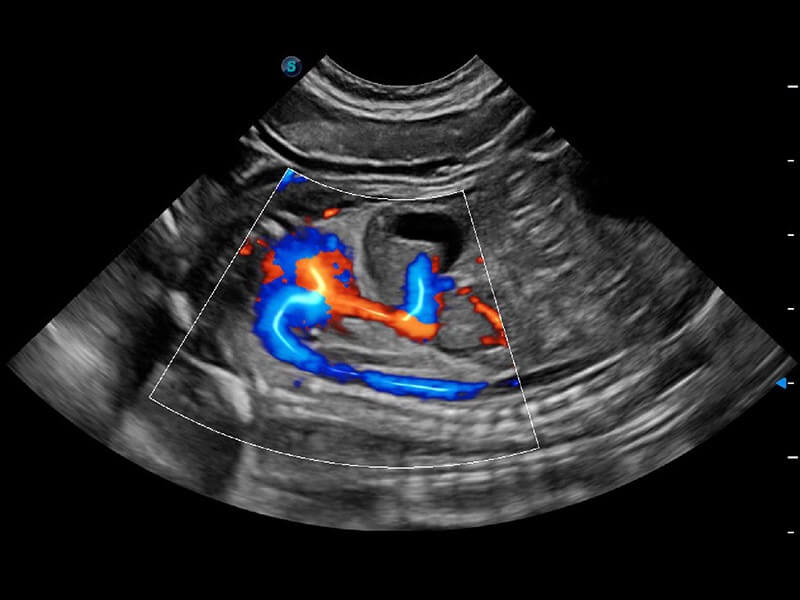

ProPet 60 作为一款高端台式动物超声设备,为动物医生的日常诊断提供了一系列贴合动物临床需求、解决临床实际问题的高级成像功能。凭借全系列高清探头,满足医生对腹部、心脏、生殖、浅表、肌骨等成像的所有需求,切实帮助您提升检查效率,提高诊断信心。

兽用彩色多普勒超声诊断系统